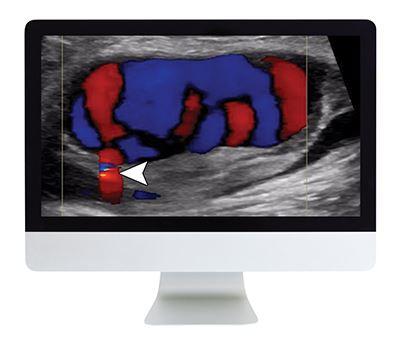

- Vascular—S. Bhatt

- Doppler Artifact—D. Rubens (didactic lecture)

- Ovarian Torsion—S. Bhatt (didactic lecture)

- Vascular—D. Rubens and S. Bhatt

- Waveform Recognition in Carotid Doppler—S. Bhatt (didactic lecture)

- Vascular Ultrasound—C. Deurdulia

- Pearls and Pitfalls of Carotid Doppler—C. Deurdulian (didactic lecture)